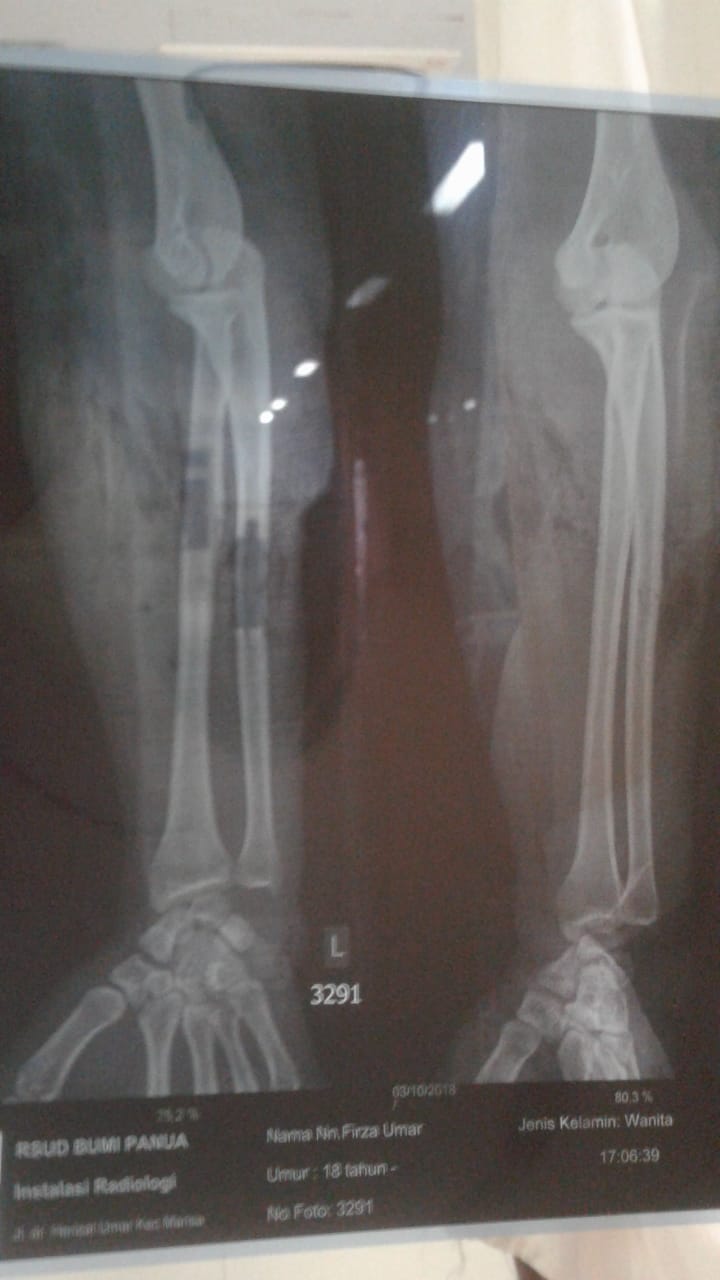

Virja Umar Himran terpaksa diamputasi tangan kirinya karena tertimpa beton bangunan dan tertusuk besi. Bahkan tangannya teriris anak tangga yang retak diakibatkan gempa yang melanda Sulawesi Tengah, pada tanggal 28 Oktober 2018 lalu.

Saat itu darah mengalir cukup banyak dan keluar tanpa henti. Di duga pembuluh darah yang mengalirkan ke bagian tangan yang terjepit seluruhnya sudah tidak bisa berfungsi, mengakibatkan tangannya mengalami kematian jaringan.

Karena sudah mengalami infeksi dan nekrosis atau kematian jaringan, esok harinya tanggal 5 Oktober 2018, dokter Spesialis Orthodi yang menangani Virja memutuskan untuk mengamputasi tangan Virja.